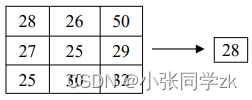

中值滤波是一种非线性处理方法,它的原理是一种基于排序统计理论的非线性空间滤波器,对于某个像素点,其像素值被其邻域的中值替换,求中值的方法如图2.8.22所示。使用中值滤波方法对MRI图像的椒盐噪声等具有很好的滤波效果,可以保持图像的边缘特征和一些细节信息。

图2.8.22求中值